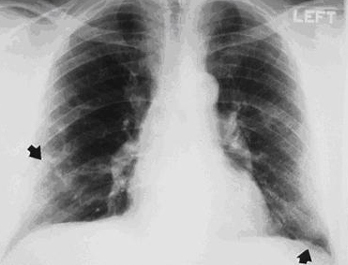

Asbestosis

Posterior-anterior view of the chest with "mesa"-like pleural thickening of the left diaphragm and "in-profile" pleural thickening of the mid zones of both the left and right lungs

From the personal collection of Kenneth D. Rosenman MD